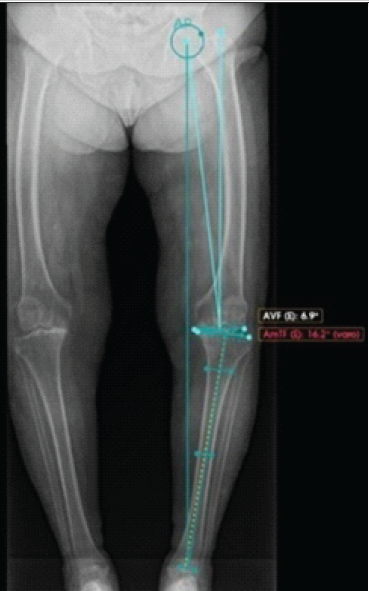

Femoral lateral bowing was defined as a coronal plane angle of ≥5°, according to Kim and Lee [5]. The lateral femoral bowing angle was measured using the Yau method, as described by Lee et al. [6], which has been shown to be highly reproducible (inter-rater reliability ≈ 0.98). Pre-operative measurements included a mechanical axis deviation of 16.2° of varus (Fig. 2), a lateral femoral bowing angle of 20.4 degrees (Fig. 3), lateral distal femoral angle of 95.2°, and medial proximal tibial angle of 89.2°.

Figure 2: Pre-operative standing long-leg anteroposterior radiograph measurement of 16.2° of varus.